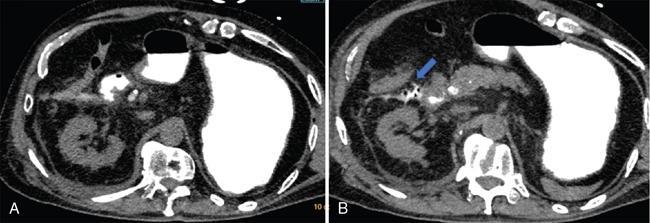

Fig. 10.17.1.3 Contrast-enhanced axial CT sections in a case of acute pancreatitis (asterisk in A); the pancreas appears diffusely bulky with peripancreatic fat stranding. Thickening of the anterior renal fascia (blue arrows in B and C) with fluid collection in the anterior pararenal space (blue arrow in D).